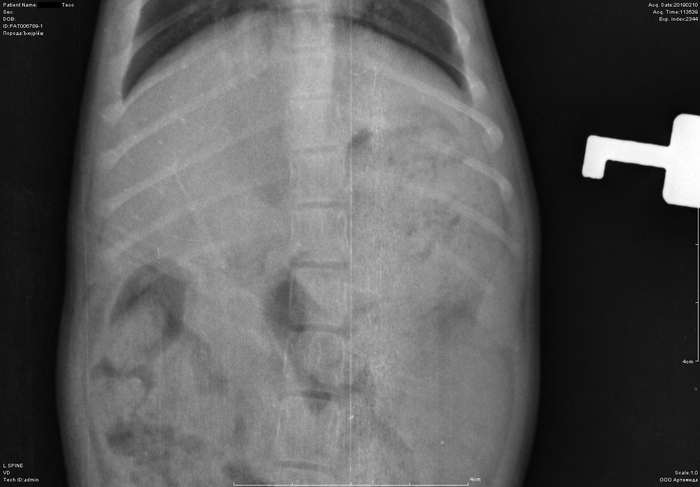

Рентген котенка

Добрый день. Котенок рожден 5 ноября 2018 года, девочка, не привита. Проглистована. Неожиданно в один момент стала припадать на задние ноги. Как бы бережет их и старается не прыгать лишний раз. Свозили два дня назад к ветеринару - всю её прощупал, говорит переломов нет, вывихов тоже. Сделали блокаду ближе в крестцу новокаина, чтобы снять симптомы. Прописал кальций в таблетках Ексел. Сейчас всё примерно так же - лапки задние бережет, но стала по активнее. Прошу специалистов, если такие тут бывают, оценить снимки, т.к. врач ещё кое-что сказал и хотелось бы услышать ваше мнение. Скан расшифровки и д/з потом приложу.

Фронтальная проекция